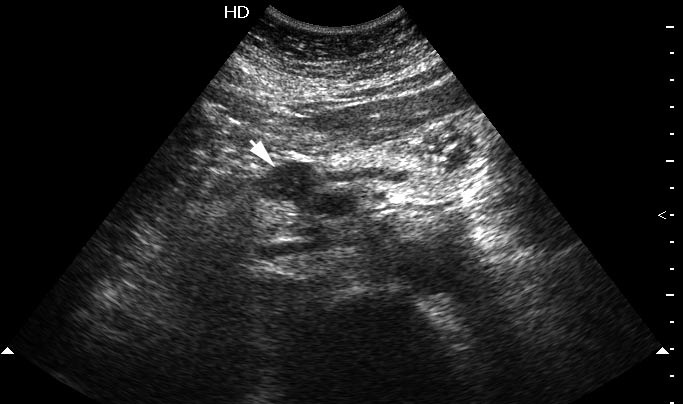

Женщина средних лет, боли в эпигастральной области. На УЗИ выявлено гипоэхогенное образование в области перешейка. Вирсунгов проток слегка расширен. При ЦДК в образовании определяется воспроизводимый кровоток.

Сонограмма панкреас, ее продольное сканирование.

Оперирована, интраоперационная цитология - злокачественных клеток не обнаружено; гистологический диагноз - тубулярная аденома.